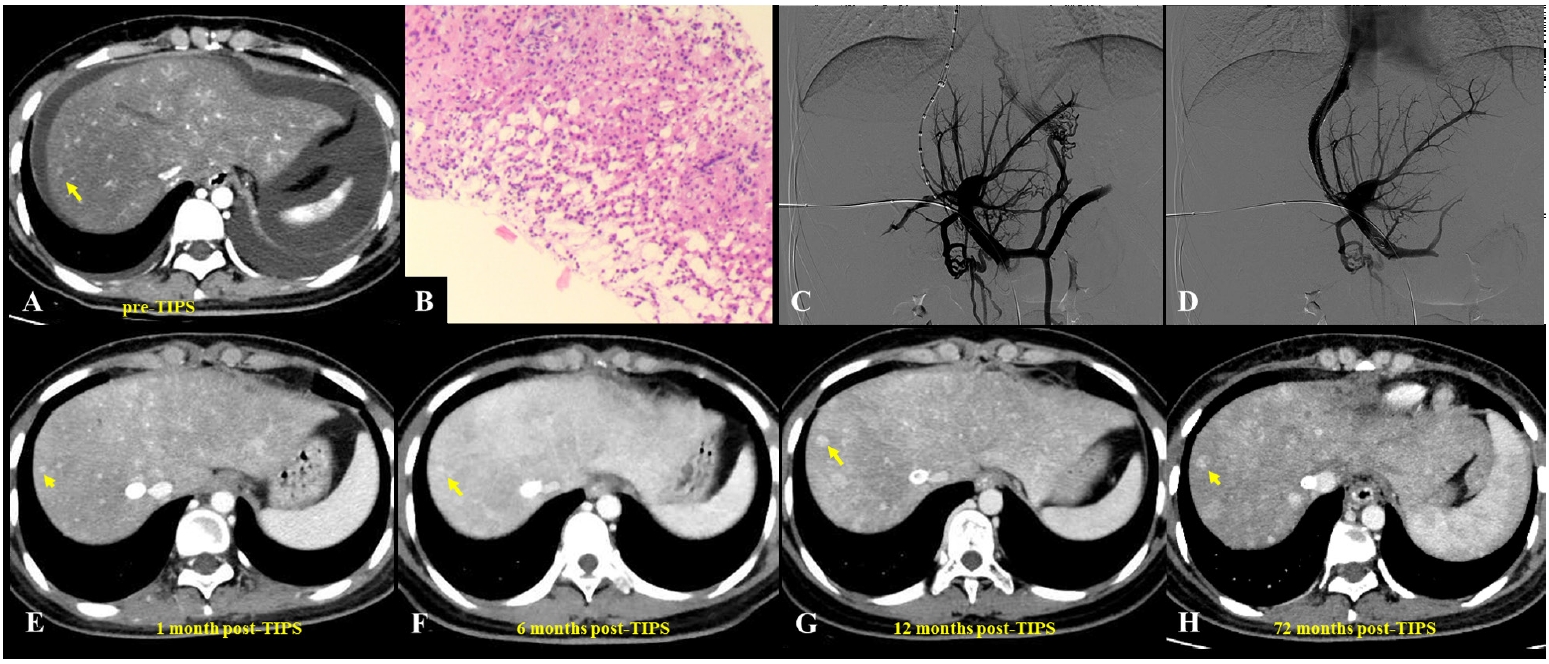

Fig. 1.A 62-year-old man diagnosed with hepatic sinusoidal obstruction syndrome 4 months after ingestion of Gynura segetum. (A) Abdominal computed tomography (CT) during the hepatic venous phase demonstrated patchy parenchymal enhancement with characteristic clover-like enhancement around the hepatic veins. Significant ascites and bilateral pleural effusions were also observed. (B) Coronal CT revealed patchy liver enhancement and narrowing (thinning) of the portal vein, accompanied by abundant ascites. (C, D) Portography before and after transjugular intrahepatic portosystemic shunt (TIPS) creation. A guidewire, introduced via the right hepatic artery, was used to provide real-time guidance during the procedure. (E–H) Post-TIPS abdominal CT showed well-defined opacification of hepatic veins with substantial resolution of both ascites and pleural effusions. Long-term follow-up CT, extending up to 24 months, confirmed homogeneous enhancement of the liver parenchyma and sustained patency of the TIPS shunt.

TIPS has emerged as an important therapeutic option for PA-HSOS patients with refractory PH or ascites, and although it has no specific contraindications for treatment, guidelines recommend considering it for patients with ineffective medical therapy, highlighting the importance of individualized assessment [

15]. Studies have shown that ascites and pleural effusions can markedly improve within a short period after TIPS placement, with previously obstructed hepatic veins often regaining patency in the short term when combined with AT (

Figs. 1,

2) [

10,

52]. Various studies have confirmed the safety and efficacy of TIPS in managing PA-HSOS (